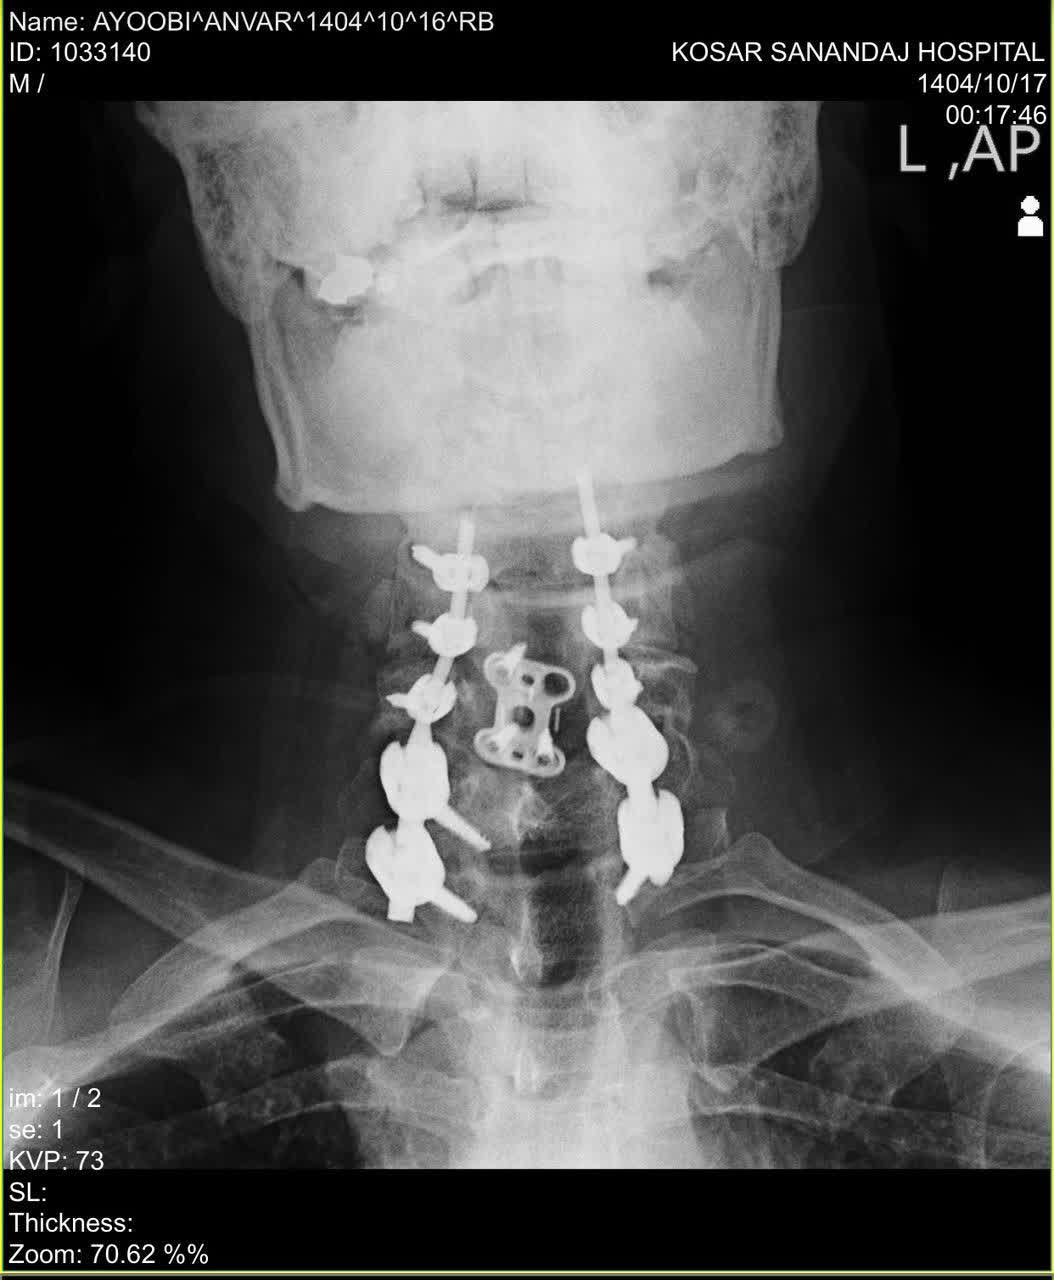

دکتر محمدی در توضیح مرحله اول جراحی گفت: در مرحله اول، از طریق برش در پشت گردن (رویکرد خلفی)، اقدام به آزادسازی وسیع نخاع (Decompressive Laminectomy از C5 تا C7) و سپس تثبیت ستون فقرات با استفاده از پیچ و میله (Posterior Cervicothoracic Fixation) کردیم. کل این فرآیند حساس تحت نظارت مداوم دستگاه نورومانیتورینگ Intraoperative انجام شد تا کوچکترین تماس یا فشاری بر نخاع یا ریشههای عصبی بلافاصله شناسایی و از بروز آسیب پیشگیری شود. خوشبختانه این مرحله با موفقیت پشت سر گذاشته شد.

وی در مورد مرحله دوم که چهار روز بعد انجام شد، توضیح داد: در این مرحله، از طریق برشی در جلوی گردن (رویکرد قدامی) به محل آسیب دسترسی پیدا کردیم. دیسک تخریب شده و بیرون زده که به کانال نخاعی فشار وارد میکرد را به طور کامل تخلیه کرده (Anterior Discectomy) و برای حفظ ثبات ناحیه، از یک کیج (Cage) مخصوص پر شده با مواد استخوانی استفاده نمودیم. در نهایت نیز با قراردادن یک پلیت (Plate) و پیچ در سطح مهرههای مجاور، تثبیت نهایی را انجام دادیم. این مرحله نیز با موفقیت کامل به پایان رسید.